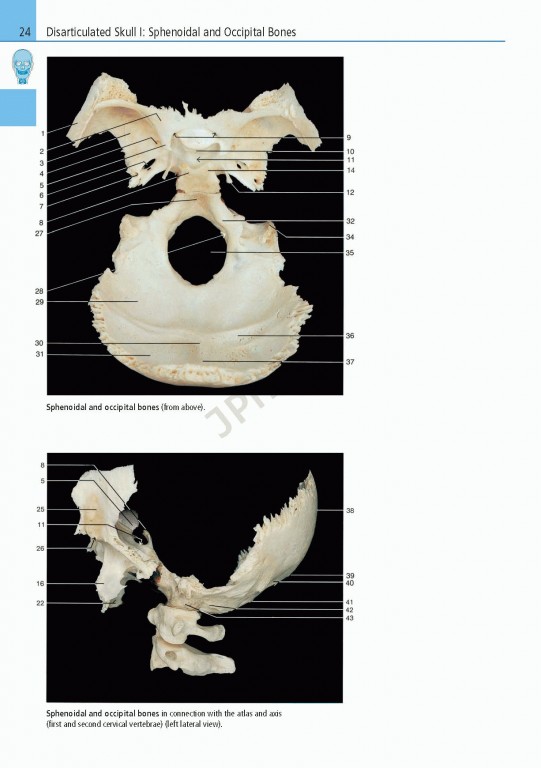

ویراست هشتم کتاب Rohen Atas Of Anatomy 2015 با استفاده از عکس‌های برجسته و کاملا رنگی از شکاف‌های واقعی جسد همراه با نقاشی‌های شماتیک و تصاویر تشخیصی ساختارهای آناتومیک را به صورت واقعی تر از تصاویر موجود در اطلس‌های سنتی به تصویر می کشد.

Prepare for the dissection lab and operating room with Anatomy: A Photographic Atlas , 8e. Featuring outstanding full-color photographs of actual cadaver dissections with accompanying schematic drawings and diagnostic images, this proven text depicts anatomic structures more realistically than illustrations in traditional atlases. Chapters are organized by region in the order of a typical dissection with each chapter presenting topographical anatomical structures in a systemic manner.

Authentic photographic reproduction of colors, structures, and spatial dimensions as seen in the dissection lab and on the operating table help you develop an understanding of the anatomy of the human body.

Dissections illustrate the topographical anatomy in layers "from the outside in" to better prepare you for the lab and operating room.